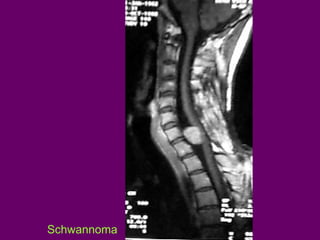

U BAO DAÂY THAÀN

KINH VUØNG COÄT

SOÁNG

a.Coù hai loaïi: Schwannoma

vaø

neurofibroma

b.Tæ leä : Thöôøng gaëp nhaát trong

oáng soáng (15-30%)

c.Vò trí : Reã sau.

-Ngoaøi maøng cöùng–ngoaøi tuyû

(70%) Ngoaøi maøng cöùng (15%) Vöaø

ngoaøi maøng cöùng vöøa ngoaøi tuyû

(15%/ Dumbbell ) Trong tuyû (1%)

d.MRI :

-Ñoàng hoaëc coù tín hieäu

thaáp treân T1W, tín hieäu cao

treân T2W.

-Schwannoma thöôøng taêng

tín hieäu maïnh sau tieâm Gd

SCHWANNOMA

Hình T1W

Bn.Nguyeãn Thò Th.

Hình T2W

Hình T1W+Gd